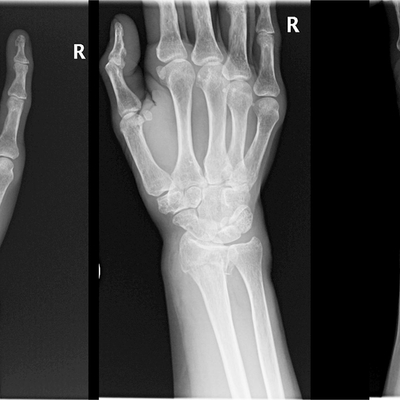

Click on an image below to view more info.